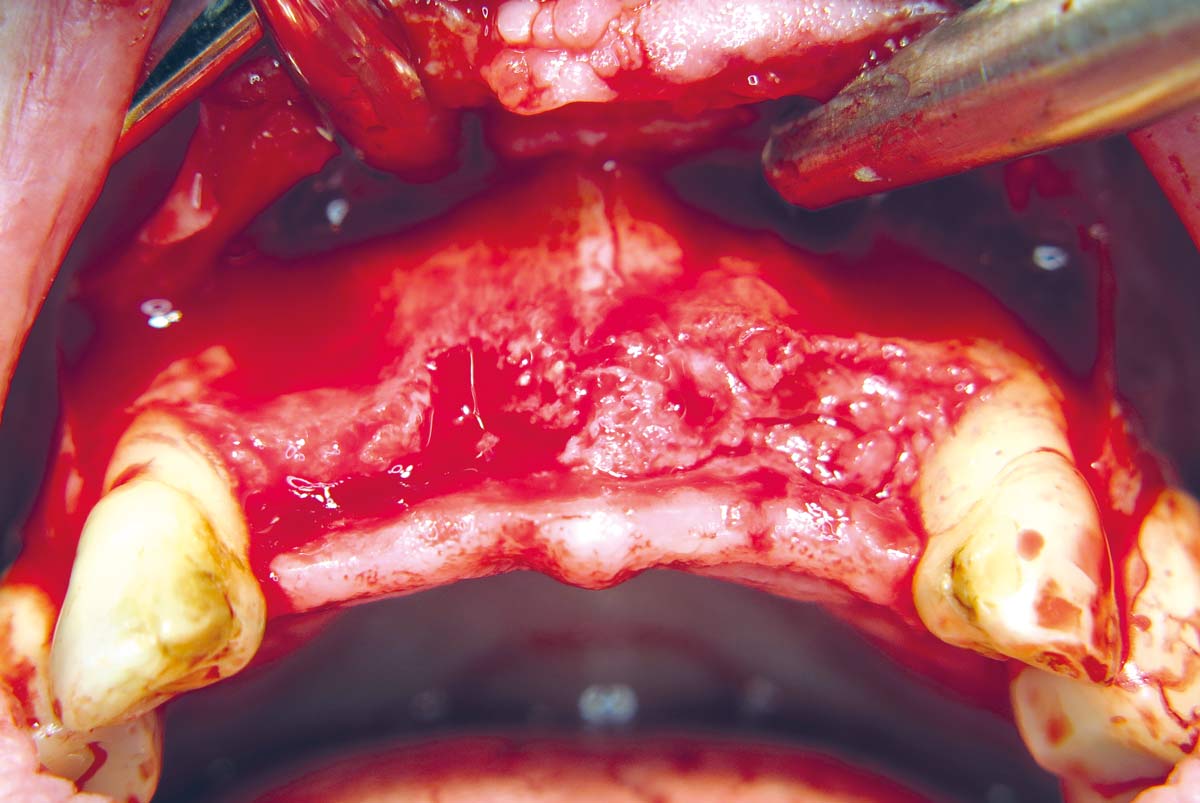

02 / 22 - Flap projection and demonstration of bone defect

Three-dimensional augmentation with maxgraft® cortico - M.Sc. E. Kapogianni